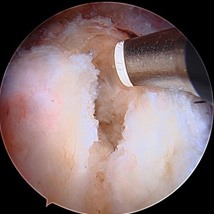

Operative Treatment for Proximal Hamstring Tears

Minimally invasive surgery can be performed either through one small incision in the posterior thigh (as seen below) or through 3-4 poke hole incisions with the use of a camera and special instruments. The tendons are reattached to the posterior pelvis (ischium) with suture anchors.